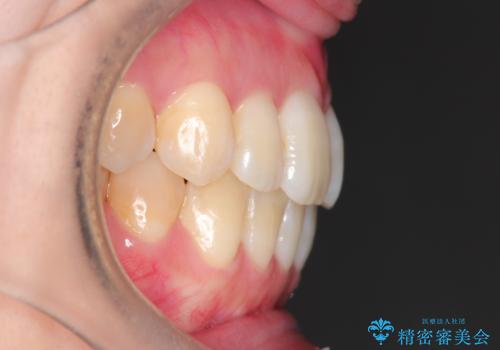

- 前歯のガタガタと、かみ合わせを改善したいとのことで来院されました。

人前でお話をするお仕事のため、装置をつけないでよいマウスピース矯正を希望されました。

下顎の歯が、上顎の歯に対して前方に位置していたので、下顎の歯を後方に移動させるのと、歯と歯の間を削りスペースを作り、歯を並べる計画としました。